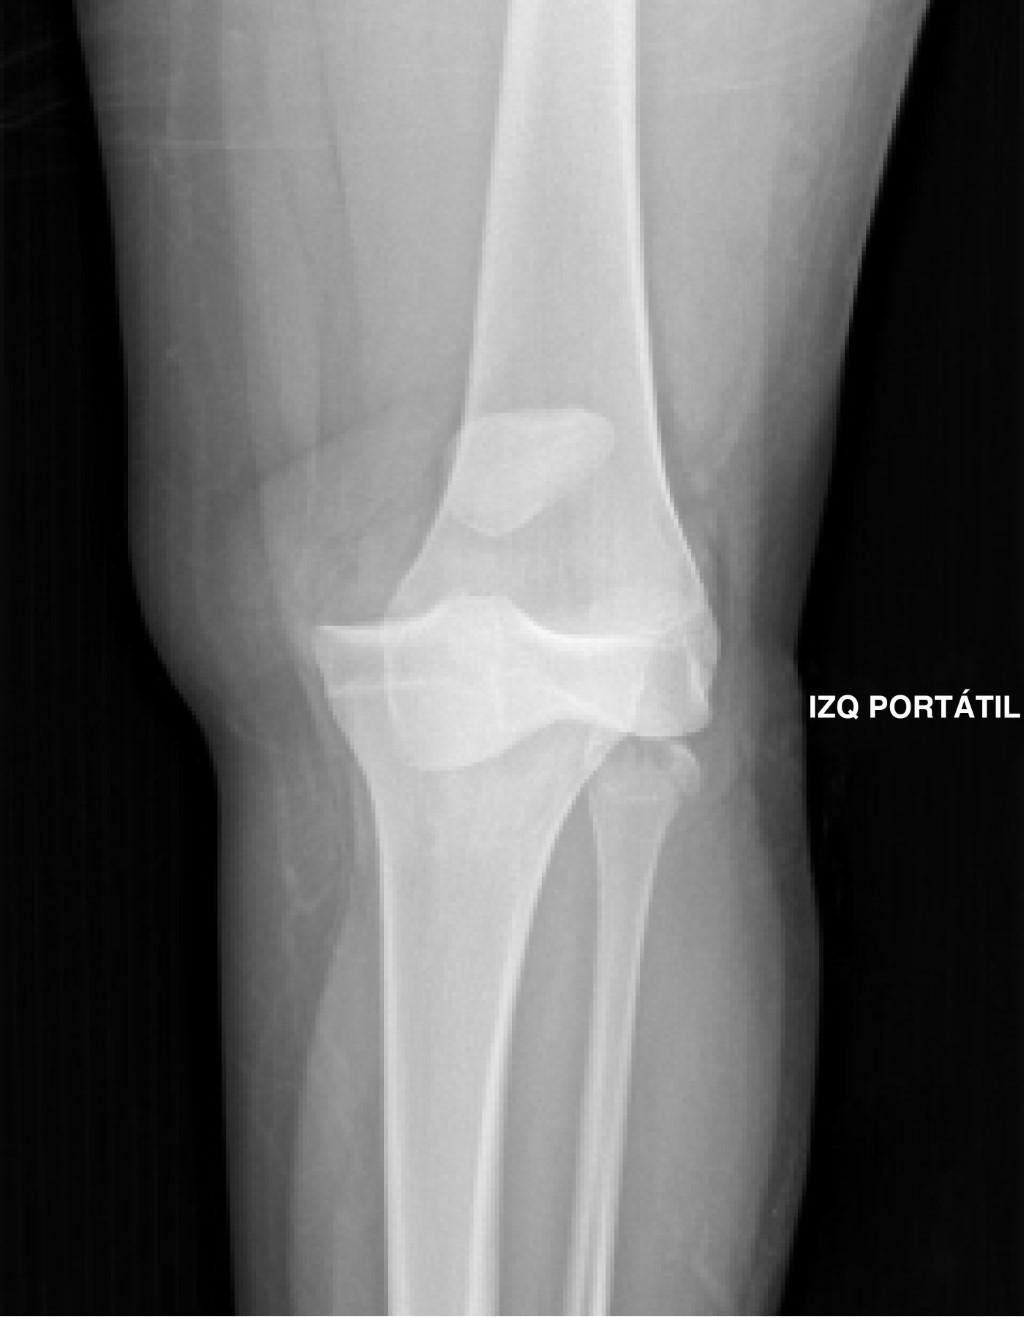

Imagenología: rayos X. El estudio con radiografía simple anteroposterior y lateral en el contexto de la luxación de rodilla se debe dividir en dos escenarios: el primero corresponde al grupo de pacientes que ingresan con una luxación evidente clínicamente, para los cuales las proyecciones AP y lateral son el estudio imagenológico inicial, permitiendo evaluar la dirección de la luxación según la clasificación de Kennedy y así definir el riesgo estimado de lesión vascular, según sea cada caso. Posterior a la realización de las maniobras de reducción es necesario efectuar nuevas proyecciones AP y lateral que permitan evaluar adecuadamente las relaciones de la articulación tibiofemoral en búsqueda de subluxaciones residuales y la presencia de lesiones asociadas (Figura 3).38,39

El segundo escenario es mucho más complejo de abordar, se presenta cuando el paciente ingresa al servicio de urgencias con la rodilla reducida, haciendo del diagnóstico de la luxación de rodilla un reto para el clínico, en el cual las radiografías iniciales tienen un papel valioso en la evidencia de hallazgos característicos que pueden sugerir el diagnóstico de luxación como la apertura de los espacios articulares tibiofemorales (Figura 4), fracturas del cóndilo femoral, fracturas de espinas tibiales anterior y posterior, signo del ligamento arcuato (Figura 5) o el signo de Segond (Figura 6).3

Figura 3

Figura 4